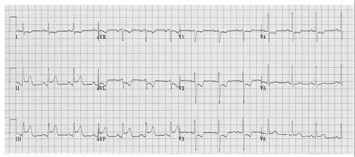

A referida paciente evolui com colapso circulatório, pulso ausente e demonstrado no eletrocardiograma apresentado. Conforme essa análise, conclui-se ser o ritmo da parada cardíaca é